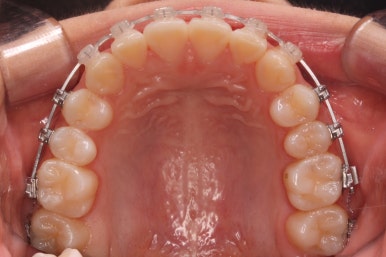

그 중 하나가 3차원 CT영상에서 이 뿌리들의 정확한 위치를 파악하고 전반적인 턱뼈의 크기 조화를 체크합니다. 필요하면 위턱뼈를 가로로 넓혀주는 악궁확장이 필요하기도 합니다.

이번 환자분은 위턱뼈가 좁은편이었고, 위턱뼈가 좁으면 콧속도 좁아서 코로 호흡하는데 문제가 있었으며 연쇄적으로 혀의 위치도 좋지 못하여 턱뼈의 성장에도 부정적인 영향을 주는 경우가 많습니다.

따라서 교정치료에 앞서 위턱은 가로로 넓혀주는 악궁확장장치(RPE)를 시행하기로 했습니다.

아래쪽이 더 시급하므로 브라켓 부착을 하여 가지런히 하기 시작했고 위쪽은 악궁확장장치를 입천장에 하여 위턱뼈를 가로로 넓혀주기 시작합니다.

악궁확장장치는 총 4-6개월 정도 부착하고 있으며 그 이후에는 입안에서 제거하게 됩니다.

윗니에도 이제 장치를 모두 붙였습니다. 아래쪽은 어느 정도 가지런해지고 나면 부족한 자리를 만들어주기 시작합니다.

치료 종료 후의 모습입니다.

치아들이 가지런하게 되었고, 나오지 못하던 치아도 잘 나와서 가지런해졌습니다.

해당 부위 앞뒤로 쓰러져 있던 치아들도 축이 바로 잡혔고, 자연스레 위-아래 치아의 중앙선도 맞아졌습니다.